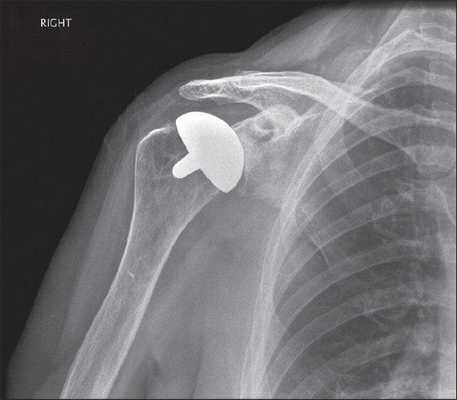

- Поверхностное. Применяется, когда минимальны повреждения головки кости пациента и много костной ткани можно сохранить. Головка обтачивается специальным инструментом, на нее «сажается» имплантат, замещающий собой поверхность сустава.

Рентген после эндопротезирования плечевого сустава